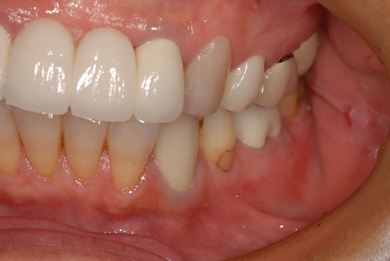

治療前

• 治療前

治療後

• 治療後